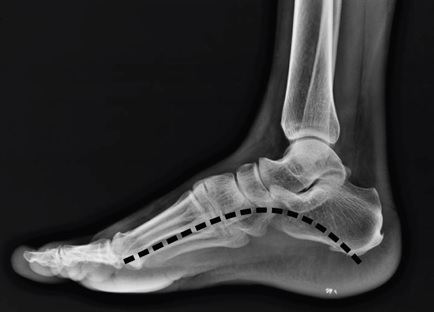

Jedním z potenciálních přispěvatelů ke ztuhlosti nohou u lidí je podélná klenba chodidla. Studie nohou prokázaly, že podélná klenba chodidla může fungovat jako pružina, ale není známo, zda lidé mohou upravit tuhost podélné klenby v koordinaci s proximálnějšími klouby, aby pomohli kontrolovat tuhost nohou během běhu.

V rámci studie bylo použito 3D snímání pohybu u 27 dospělých účastníků běhajících na běžeckém pásu. Pomocí modelů ohybu paprsku a kinematických modelů chodidla se vypočítala tuhost podélné klenby.

Bez ohledu na to, který typ nohy byl použit, bylo zjištěno, že účastníci významně zvýšili kvazi ztuhlost podélné klenby mezi běhy s nízkou a vysokou frekvencí, což odráží změny v kotníku, koleni a noze celkově.

U typů chodidel bylo zjištěno, že model zahrnující sílu triceps surae do ohybové síly na chodidle produkoval nerealisticky vysoké odhady námahy podélné klenby, což vědce vedlo k odrazování od tohoto modelovacího přístupu. Kromě toho zjistili, že mezi účastníky neexistuje konzistentní korelace mezi hodnotami výšky podélné klenby a kvazi tuhosti, což naznačuje, že statická měření výšky podélné klenby nejsou dobrými prediktory dynamické funkce.

Celkově tato zjištění podporují hypotézu, že lidé dynamicky upravují tuhost podélné klenby během běhu v souladu s jinými strukturami nohy.